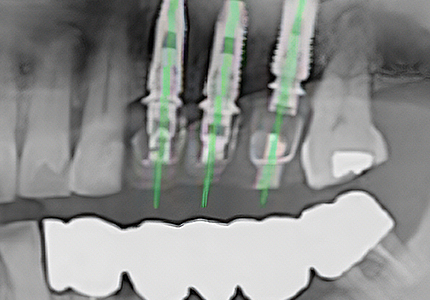

• Guide-Assisted Surgery

The custom surgical guide is seated intraorally prior to surgery, enabling systematic placement at the planned position with minimal margin of error.

Natural implant placement at the simulation-planned position, with a prosthesis that feels just like your own natural tooth.

Surgery is performed through a small access opening just large enough for implant placement — without gingival incision — offering the advantage of minimal pain and faster recovery.